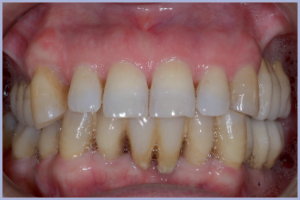

Paziente femminile non fumatrice di anni 65. La paziente si presenta in data 14/03/06 con formula dentaria superiore 15-14-13-12-11-21-22-23 e inferiore 35-34-33-32-31-42-43-44-46-47, malattia parodontale cronica dell’adulto con presenza di tartaro, sanguinamento e sondaggio parodontale su tutti gli elementi (figg. 1, 2); la paziente rifiuta a priori la protesi parziale rimovibile per motivi funzionali.

Il controllo clinico e radiografico a due anni e mezzo dall’applicazione della protesi definitiva evidenzia un buon mantenimento del lavoro implantare e protesico (figg. 33-38), la paziente, molto migliorata nella compliance ai dettami della salute orale dal momento della prima visita in poi, si mantiene collaborante nell’igiene domiciliare e nei controlli di igiene semestrale.